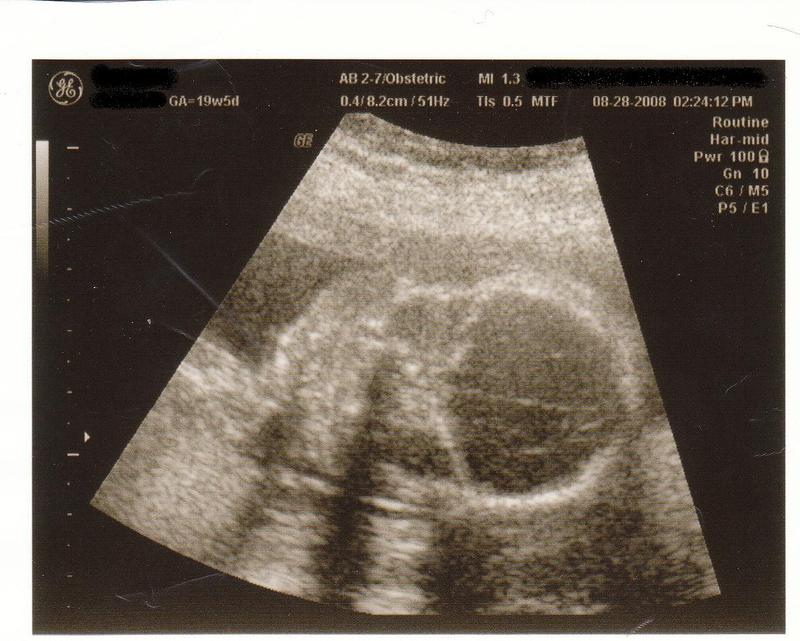

ChloeAnn wrote:

Heres ya one to freak ya out vinia. just went to the doc the 28th to find out Im having a boy, and this is one of its head lol. (I wont show the "its a boy" one >_>SMILEY

It always freaks me out cuz they dont look human lol. I'll post one when Im 'bout due and I get my 3-D ultrasound. Now THAT is scarey!!

It may be a tad big hehe but yeah she's due on the 14th of jan xD